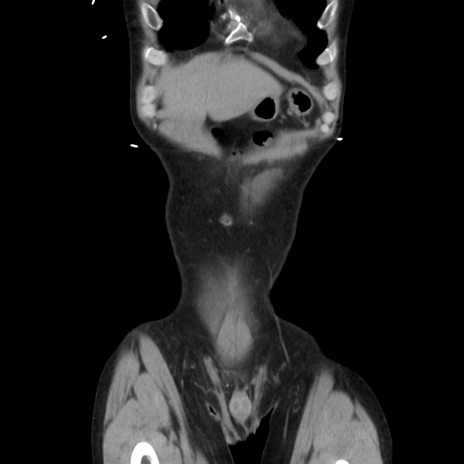

症例37(冠状断像)

【症例】40歳代 男性

【主訴】腹痛

【現病歴】4時間ほど前に電車に乗車中に臍部上より腹痛出現。徐々に増悪し起立困難となり、救急外来受診。生ものは数日食べていない。今朝お雑煮を食べた。

【身体所見】BT 36.8℃、BP 117/84mmHg、HR 91/min、SpO2 97%、苦悶様、腹部:臍上部広範囲圧痛あり、反跳痛±

【データ】WBC 8100、CRP 0.03